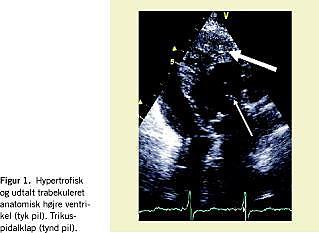

En 76-årig tidligere rask kvinde med et højt funktionsniveau blev akut indlagt med træthed, der havde varet i tre uger, samt svimmelhed og åndenød. Ved den objektive undersøgelse fandtes patienten normotensiv og kardielt velkompenseret. Pulsen var regelmæssig (61 pr. minut), og der kunne høres en styrke to systolisk uddrivningsmislyd over basis cordis. Elektrokardiogrammet viste sinusrytme med førstegrads AV-blok og QS-konfiguration i inferiore afledninger. Telemetri afslørede intermitterende andengrads AV-blok, Mobitz type 2 med ledsagende bradykardi (40 pr. minut). Ekkokardiografisk fandtes at venstre atrium via trikuspidalklappen førte til en hypertrofisk og trabekuleret højre ventrikel (Figur 1). Systemventriklens systolefunktion var let nedsat. Aorta afgik fortil i forhold til a. pulmonalis. Der fandtes let turbulent antegradt flow, som svarede til systemventriklens udløbsdel, men ingen obstruktion. Aortaklappen var trikuspid og let insufficient, men der var ingen stenose. Der var let trikuspidalinsufficiens, ingen ventrikelseptumdefekt eller pulmonal stenose. Patienten blev overflyttet til et center med landsdelsfunktion i kongenit hjertesygdom, og fik på indikationen symptomgivende andengrads AV-blok og kronotrop inkompetence ukompliceret implanteret en tokammer-pacemaker (DDD-modus). Efterforløbet var ukompliceret, og patienten blev udskrevet uden medicin. Ved opfølgende tremåneders kontrol var patienten symptomfri, og ekkokardiografisk fandtes der uændrede forhold.

Ekkokardiografi hos patienter med KKT er sædvanligvis vanskelig at tolke, når man ikke forventer diagnosen. Mistanken rejses typisk med baggrund i 1) et meget midtstillet hjerte (eventuelt dekstrokardi), 2) »forkert« forløb af de store kar med aorta beliggende fortil, 3) udtalt apikal trabekulering af systemventriklen og 4) AV-klappen i systemventriklen med chordae som hæfter til septum (tricuspidalklap og højre ventrikel), mens chordae i den subpulmonale ventrikel kun hæfter til den frie væg (mitralklap og venstre ventrikel).